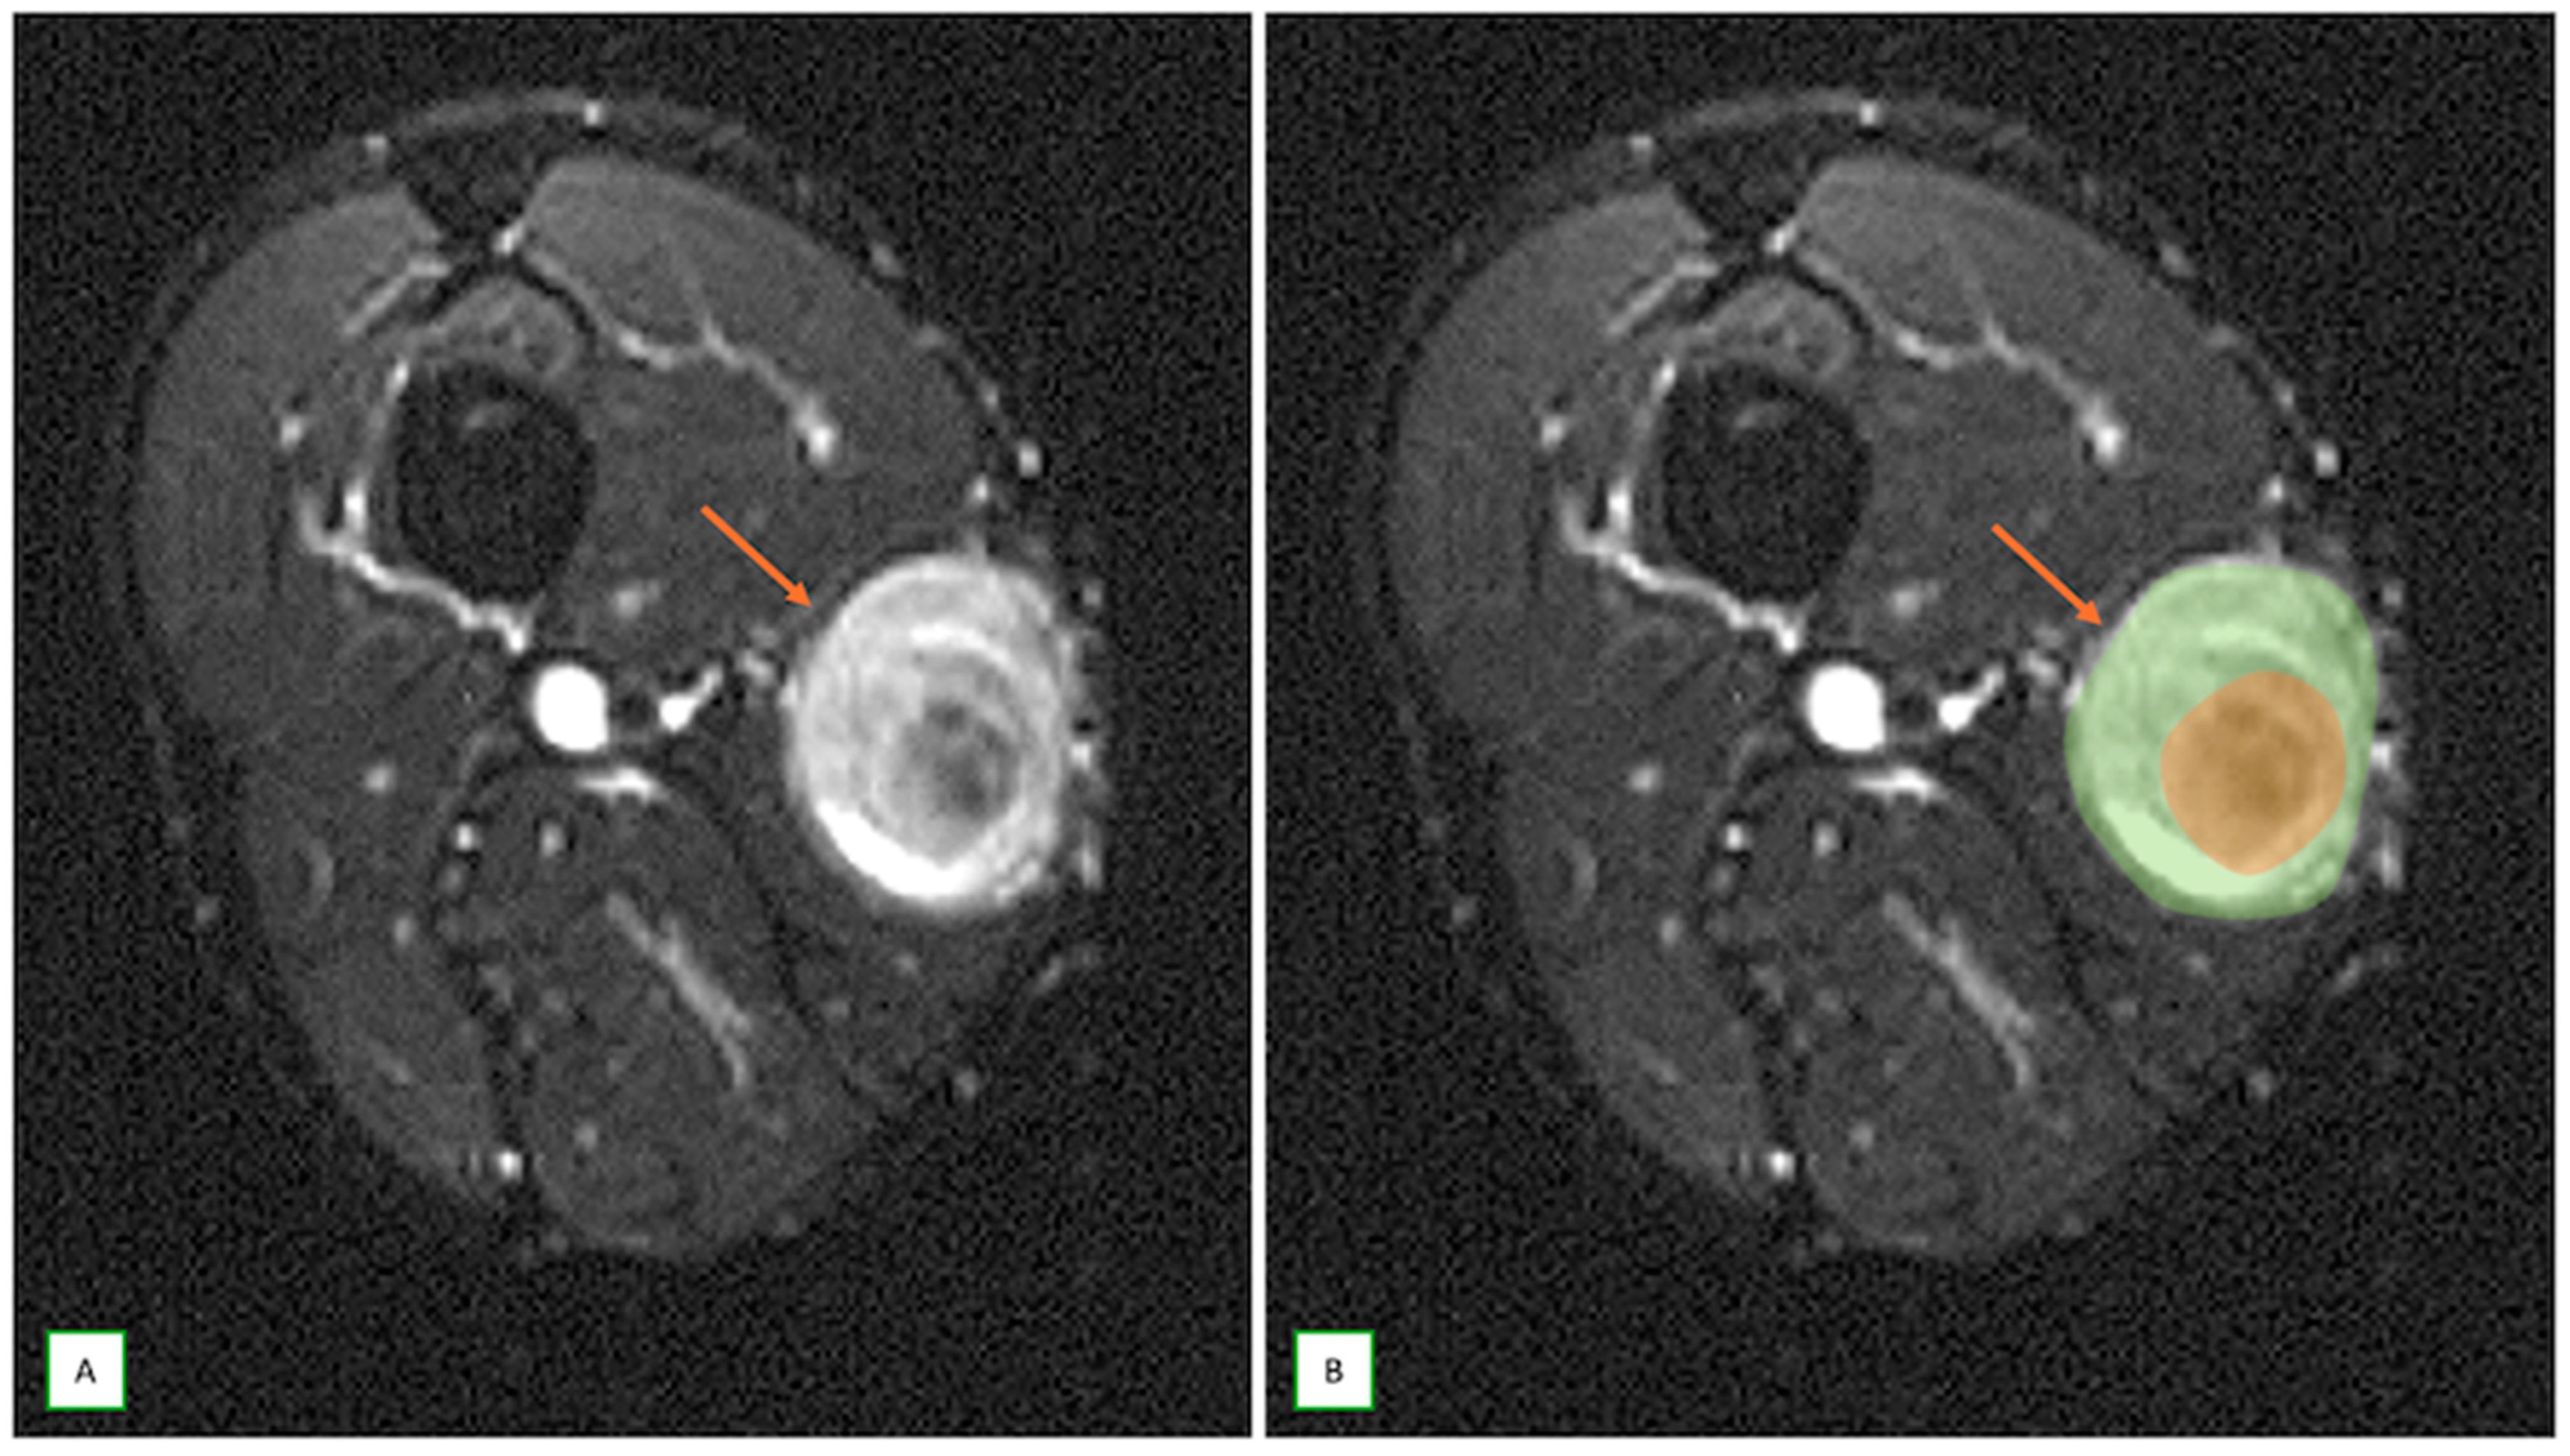

- Primary Sarcomas: Soft-tissue sarcomas are uncommon, accounting for just over 1% of adult malignancies. Synovial sarcoma, clear cell sarcoma, and epithelioid sarcomas are known to involve peripheral nerves. CT/MR reveals a large soft tissue mass with areas of necrosis or calcification and heterogeneous contrast enhancement. F-18 FDG uptake is useful for both tumor staging and treatment assessment (Figure 26, Figure 27 and Figure 28).